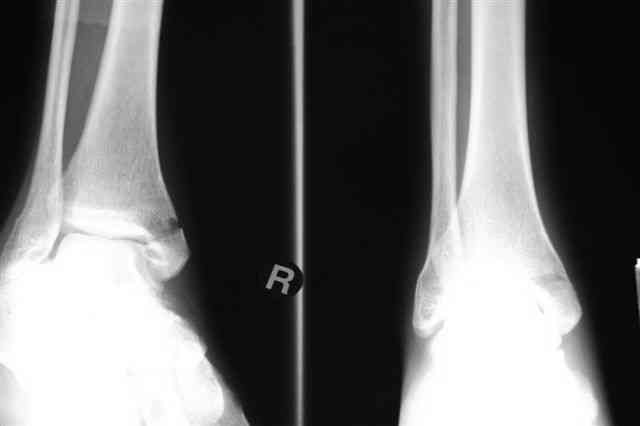

Лодыжку так ипрооперировал двумя 3.5 мм шурупами пришлось открыть - закрыто не удалось адекватно отрепонировать, при открытии - надкостничная

интерпозиция.

Снимки бедра и голеностопа еще не сфотографировал, обязательно представлю на форум

В приложении отправляю послеопер. снимки бедра и лодыжки обсуждаемого вчера больного.